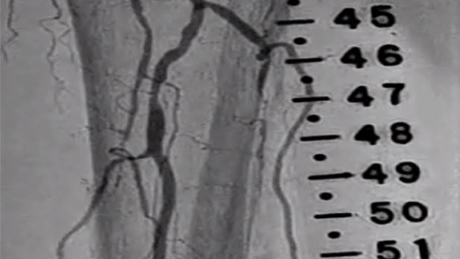

Peripheral Rotablator™

Rotational Atherectomy System

Case Studies